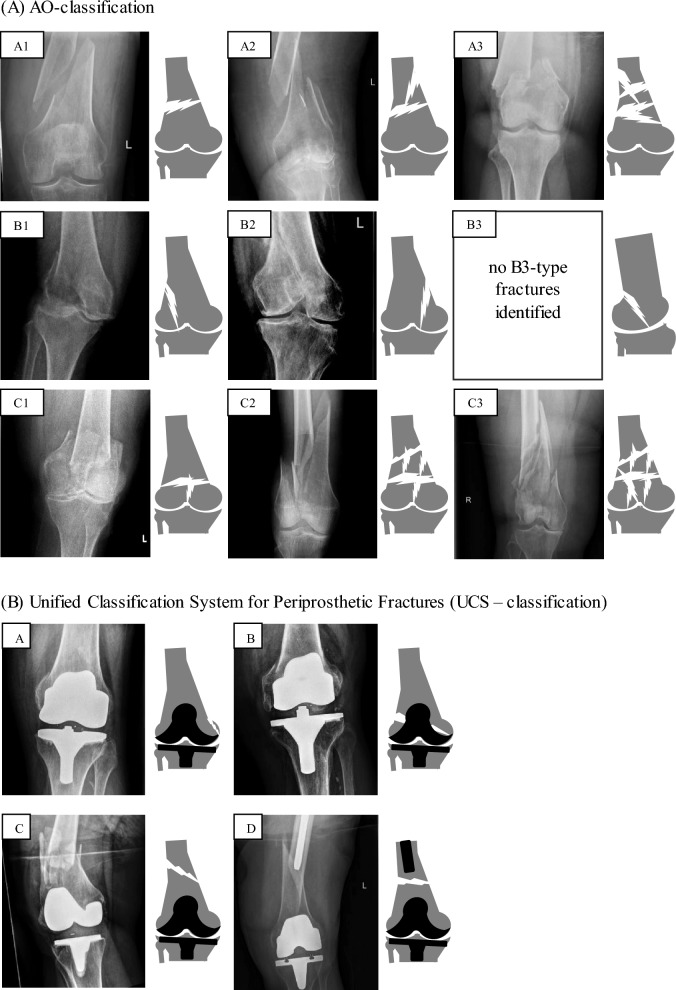

Results: In total, 206 patients (167 female, 39 male) with an average age of 75 (SD 16) years were diagnosed with a fracture of the distal femur. One hundred fourteen of these patients were treated surgically by means of plate osteosynthesis. In 13 cases (11.41%), a revision procedure had to be performed. The indication for surgical revision was mechanical failure in eight cases (7.02%) and septic complication in five cases (4.39%). Periprosthetic fractures were more likely to cause complications overall (19.6% versus 4.76%) and further included all documented septic complications. The analysis of modifiable surgical factors in the context of plate osteosynthesis showed higher complication rates for cerclage in the fracture area compared with plate-only stabilizations (44.44% versus 22.22%).

Conclusions: The data show an increased amount of revisions and a significantly higher number of septic complications in the treatment of periprosthetic fractures of the distal femur compared with non-periprosthetic fractures. The detected combination of plates together with cerclage was associated with higher complication rates. Level of evidence Level III retrospective comparative study.